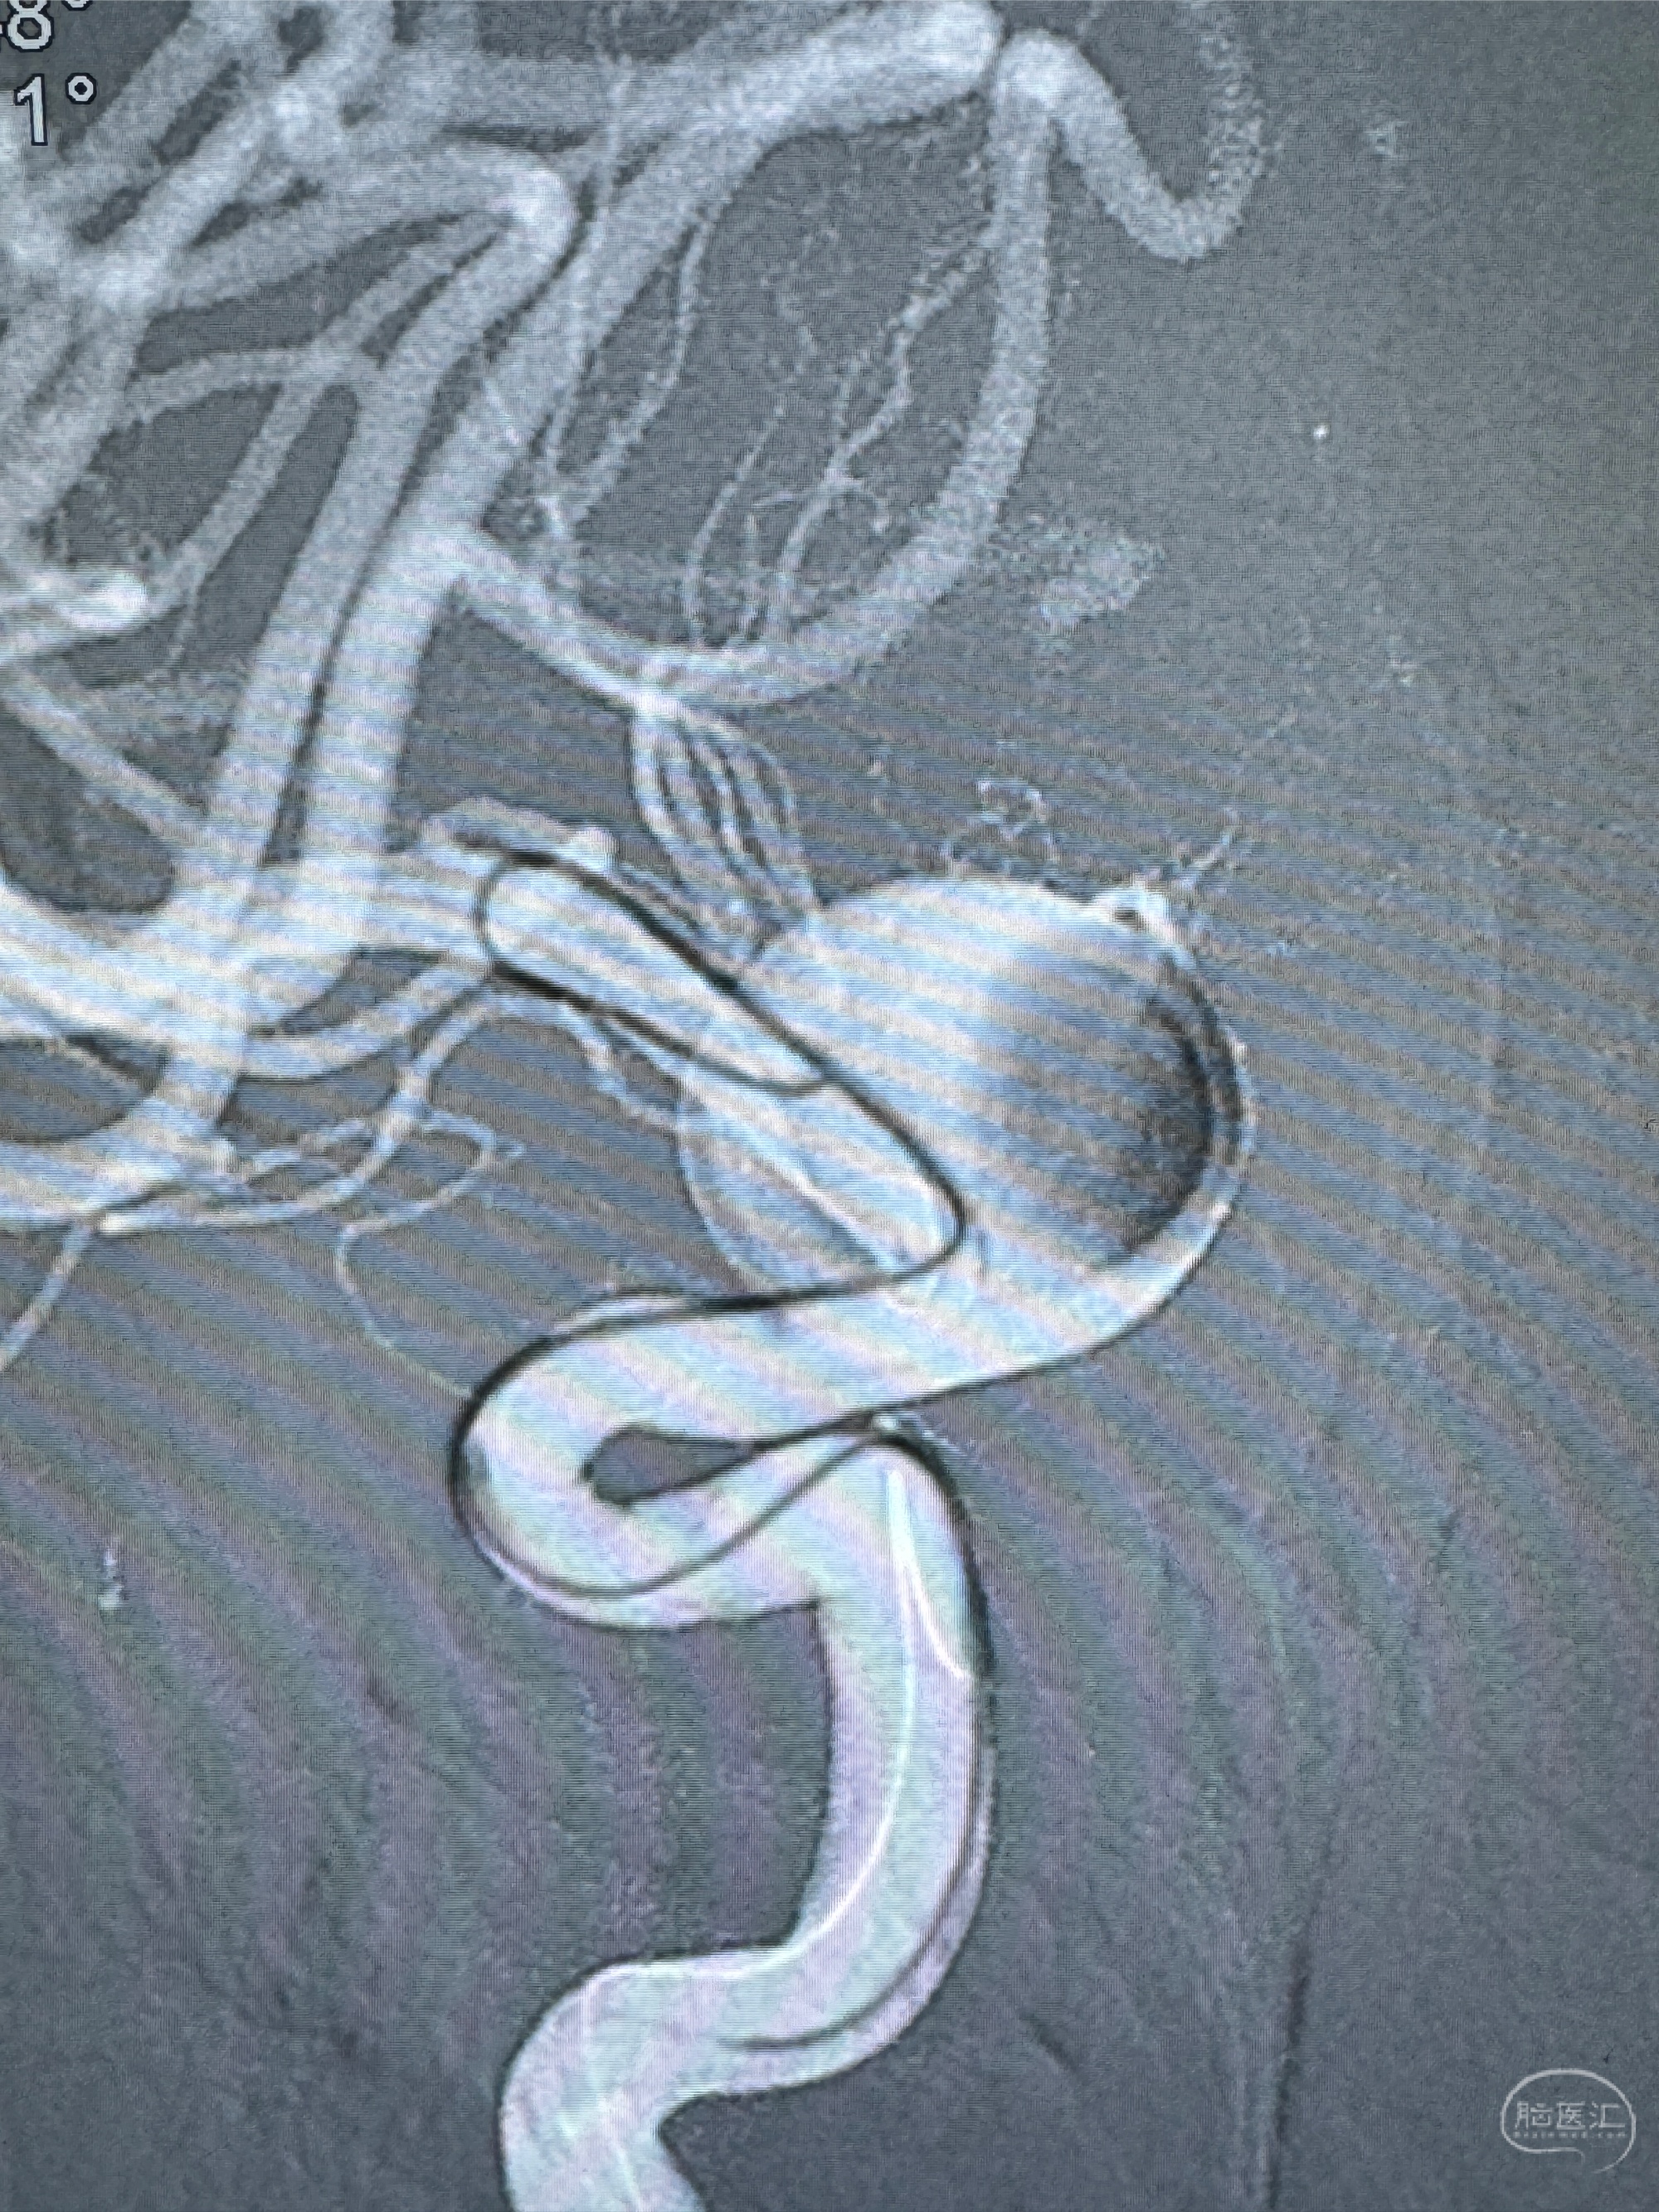

4.5-30mmTurbridge密网支架,于M1近心端打开

透视下支架释放满意

多角度显示支架打开情况

造影显示支架贴壁情况

透视可见红圈部分为支架导管的头端

手推冒烟显示支架位置及展开情况,箭头为支架导管的位置

尝试回收支架失败,只能考虑释放支架了

逐帧图像展示歪着脖子释放支架,旁边吩咐助手手机摄影、拍照留像(透视机不能留影像)